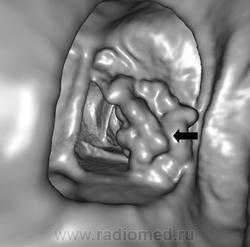

После появления спиральной КТ (СКТ) в 1989 г. метод стал объемным. При СКТ постоянно включенная рентгеновская трубка вращается вокруг непрерывно движущегося стола. Соответственно этому существенно возросло пространственное и временное разрешение метода, уменьшился риск пропустить мелкие патологические очаги. Метод стал стандартизованным. Следующим шагом (1999 г.) стало появление мультиспиральной КТ (МСКТ). Системы МСКТ первого поколения могли выполнять одновременно 4 среза толщиной от 0,5 мм за один оборот трубки (длительность его удалось сократить до 0,5 с). В настоящее время основной парк МСКТ составляют приборы с 16-64 рядами детекторов, у которых время оборота трубки составляет всего 320-350 мс, а толщина среза - 0,5 с. В 2008 г. появились приборы с 256 и 320 рядами детекторов. В настоящее время все новые системы КТ являются мультиспиральными. Благодаря техническому прогрессу, КТ стала применяться в областях, ранее недоступных для нее. Появилась КТ-ангиография, метод стал использоваться для визуализации полых органов. Были созданы методики КТ-колонографии и гастрографии. Было доказано, что диагностическая эффективность КТ-колоноскопии сопоставимо с таковой традиционной фиброволоконной колоноскопии. Учитывая быстроту выполнения и необременительность КТ-колонографии пациентов, обсуждается целесообразность применения этого метода для скрининга рака толстой кишки.

Ирригоскопия по-прежнему является одним из важнейших методов исследования всех отделов толстой кишки. Она дополняет данные колоноскопии и позволяет получить более полную информацию о состоянии органа. Одно из самых частых показаний к ирригоскопии – диагностика рака толстой кишки, полипов и дивертикулов. При ирригоскопии рак толстой кишки виден как дефект наполнения с четкой границей между неизмененной слизистой оболочкой и опухолью; выявляются признаки ригидности кишечной стенки. Нередко участок опухолевого поражения вызывает циркулярное сужение просвета кишки (симптом «яблочного огрызка»). Рентгенологические проявления рака толстой кишки зависят от гистологической формы опухоли, локализации и степени ее распространения. МСКТ и в особенности методика КТ-колонографии могут служить альтернативой ирригоскопии в скрининге и диагностике рака толстой кишки. КТ позволяет лучше видеть изменения кишечной стенки и стадировать заболевание.